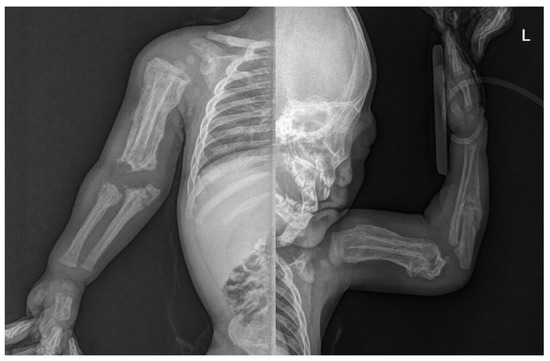

Skin lesions such as bruises or abrasions were not observed in the extremities, but an extensive periosteal reaction with transverse fractures was observed in both upper and lower long bones (Figure 2). There was no specific history of injury. Radiographs showed multiple fractures of both femurs, right tibia, and both ulna in various stages of healing. Spiral fractures were observed in the right tibia and right ulna (Figure 3).

Figure 2. Infantogram and radiograph showing extensive periosteal reaction with multiple fractures in both upper and lower long bones.